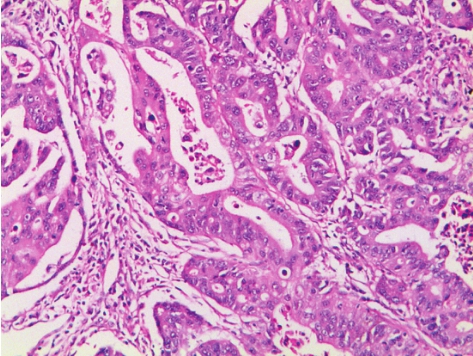

具有规则的腺体结构,常与化生的肠上皮非常相似(图3-13)。

图3-13 胃腺癌

肿瘤由分化较好的管状腺体构成,腺体形态不规则。